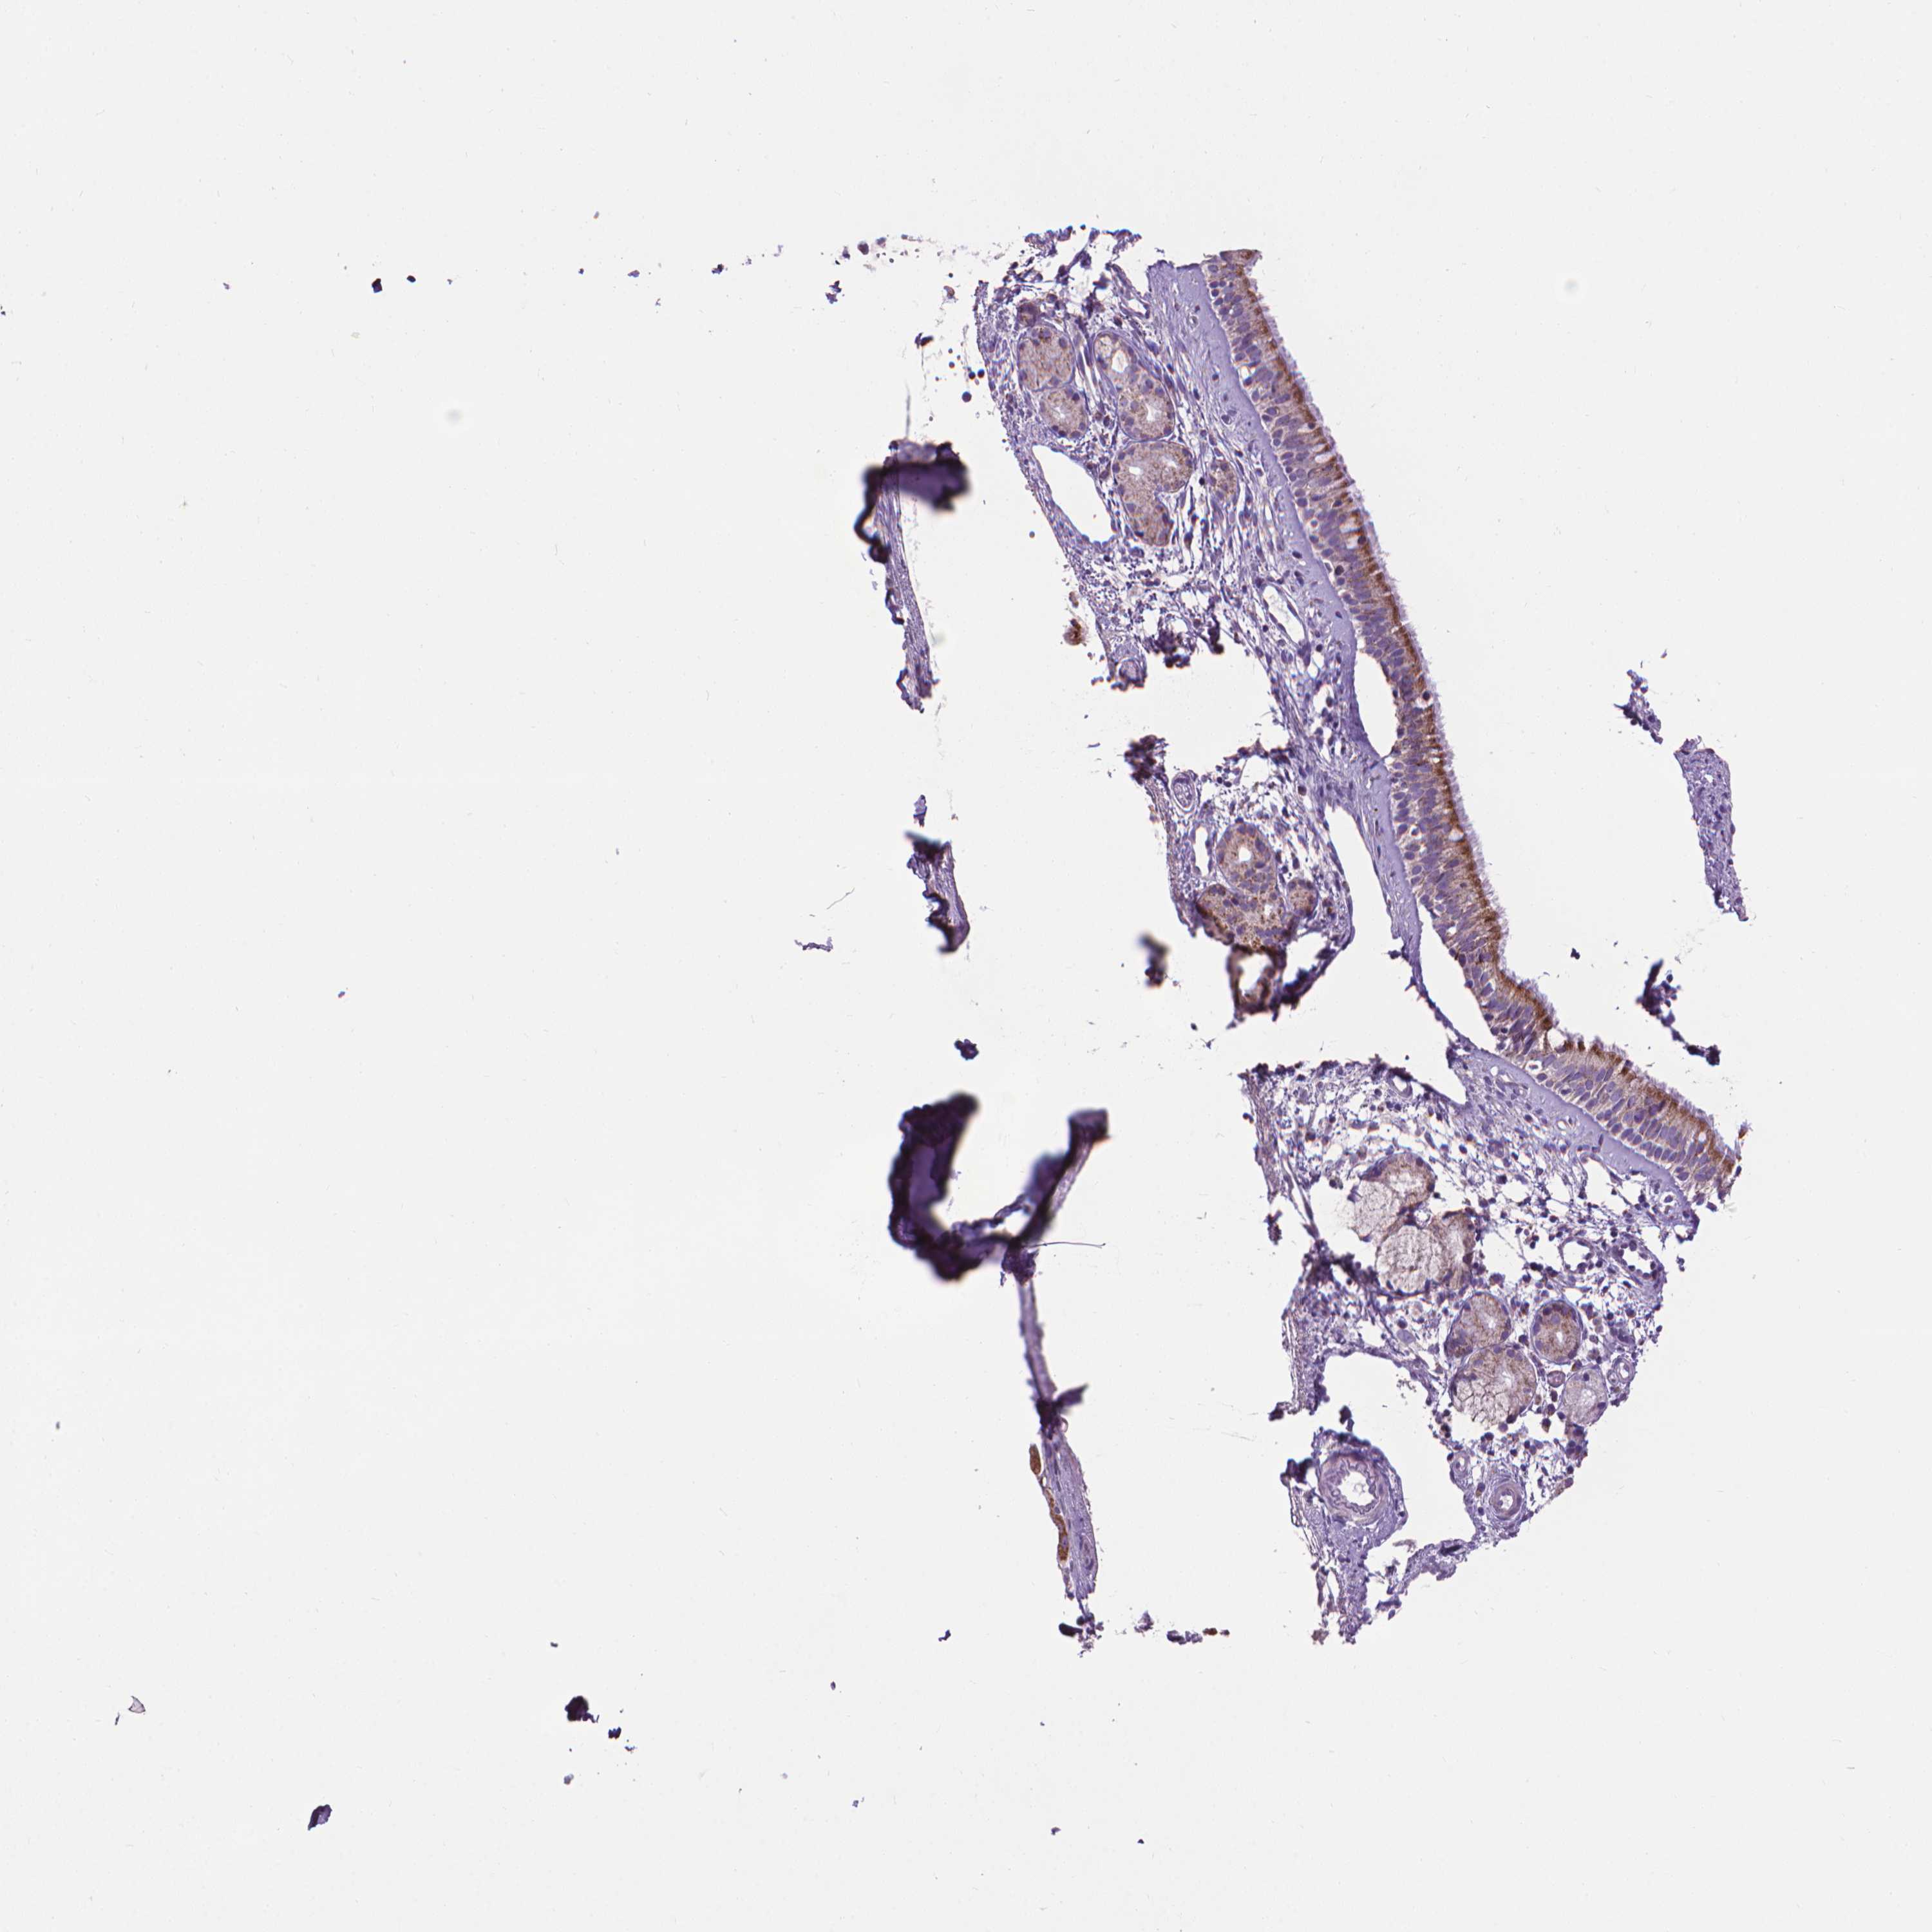

NASOPHARYNX - Antibody stainingi

Antibody staining in the annotated cell types in the current human tissue is reported as not detected, low, medium, or high, based on conventional immunohistochemistry profiling in selected tissues. This score is based on the combination of the staining intensity and fraction of stained cells.

Each image is clickable and will lead to virtual microscopy that enables deeper exploration of all samples and also displays staining intensity scores, fraction scores and subcellular localization as well as patient and tissue information for each sample.

Antibody HPA030780Antibody CAB005885Antibody CAB072343

Respiratory epithelial cells HighHighHigh